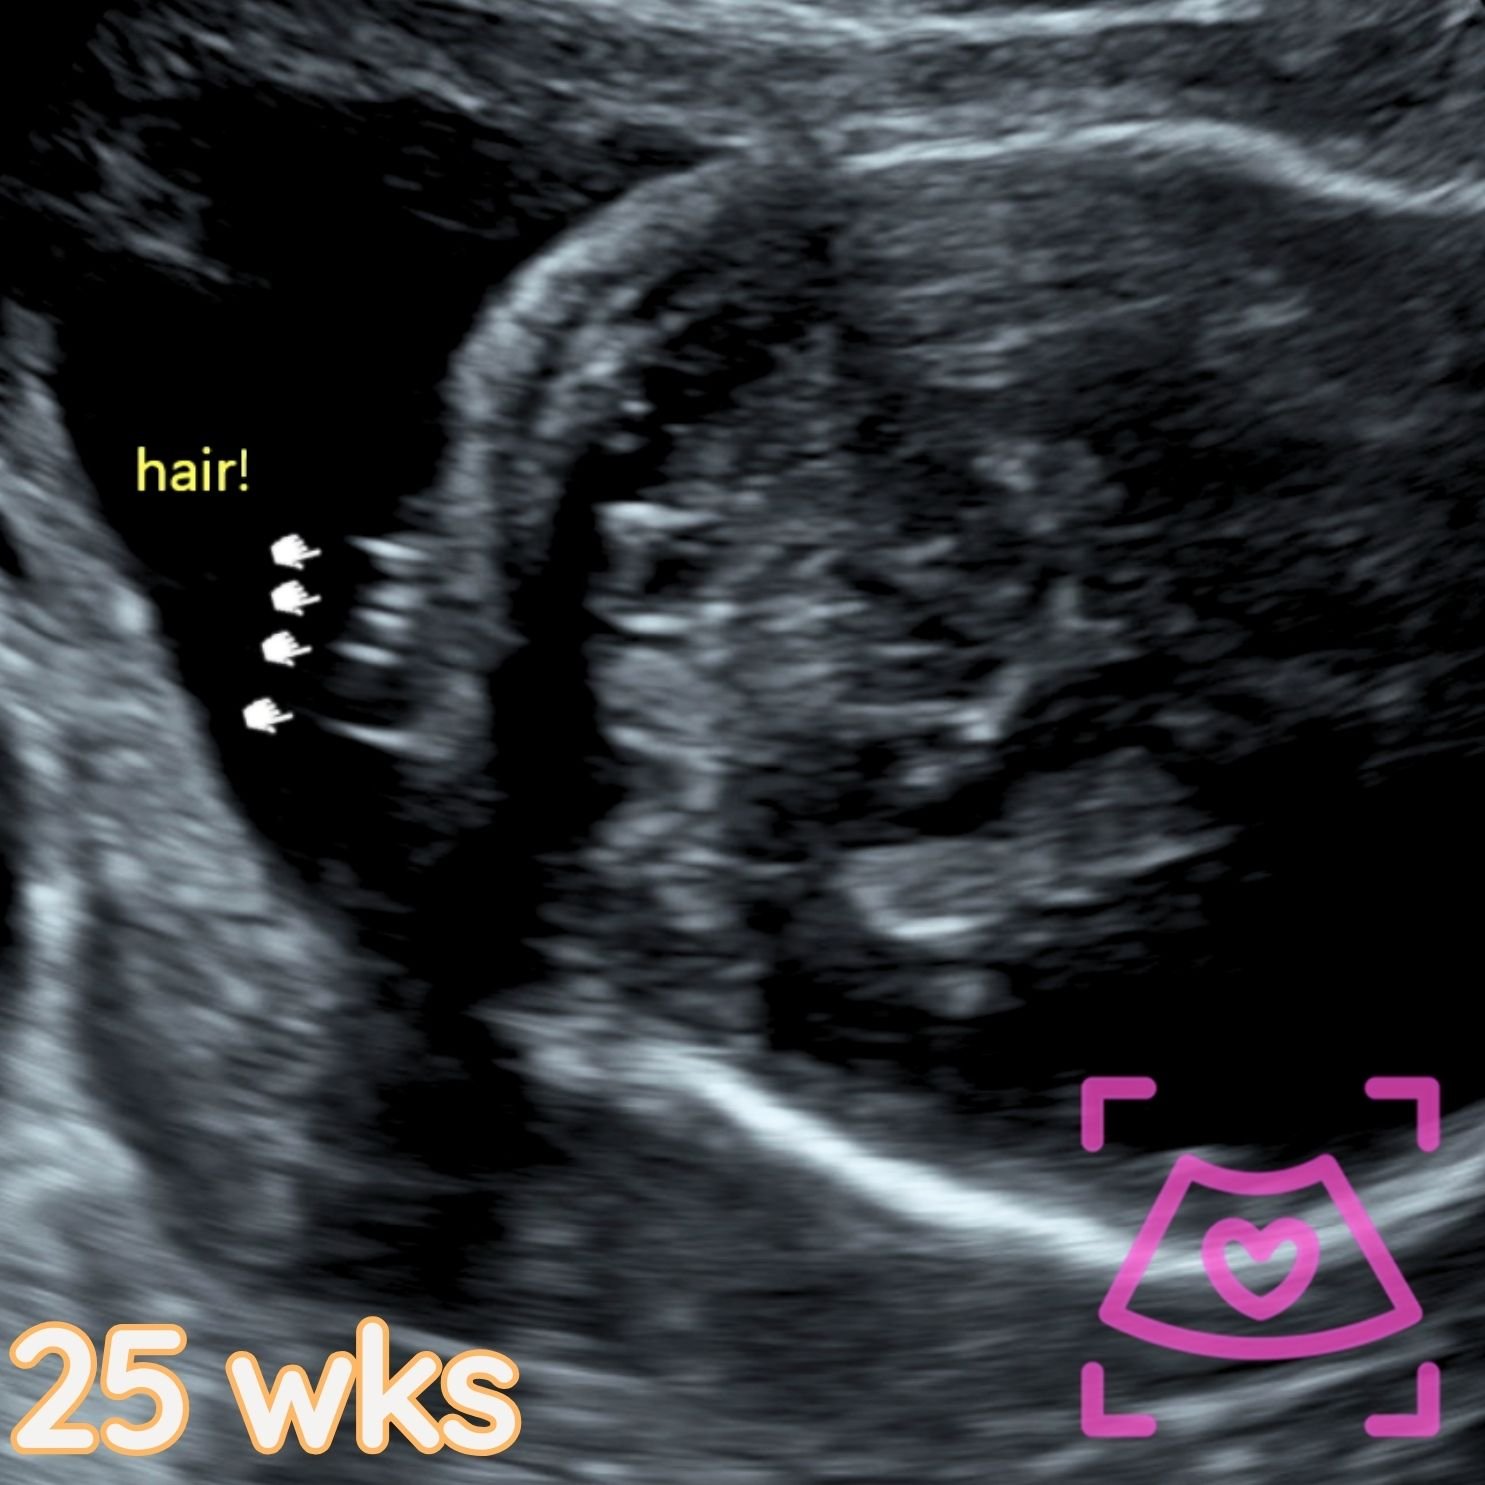

All ultrasounds at this facility are performed abdominally (on top). See examples below from 5-40 weeks! Recommended times can be found on the Services Page and when booking.

2nd Trimester